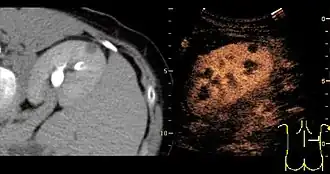

Kidney

Most renal cell carcinomas are now found incidentally.[19] Tumors less than 3 cm in diameter less frequently have aggressive histology.[20]

A CT scan is the first choice modality for workup of solid masses in the kidneys. Nevertheless, hemorrhagic cysts can resemble renal cell carcinomas on CT, but they are easily distinguished with Doppler ultrasonography (Doppler US). In renal cell carcinomas, Doppler US often shows vessels with high velocities caused by neovascularization and arteriovenous shunting. Some renal cell carcinomas are hypovascular and not distinguishable with Doppler US. Therefore, renal tumors without a Doppler signal, which are not obvious simple cysts on US and CT, should be further investigated with contrast-enhanced ultrasound, as this is more sensitive than both Doppler US and CT for the detection of hypovascular tumors.[21]